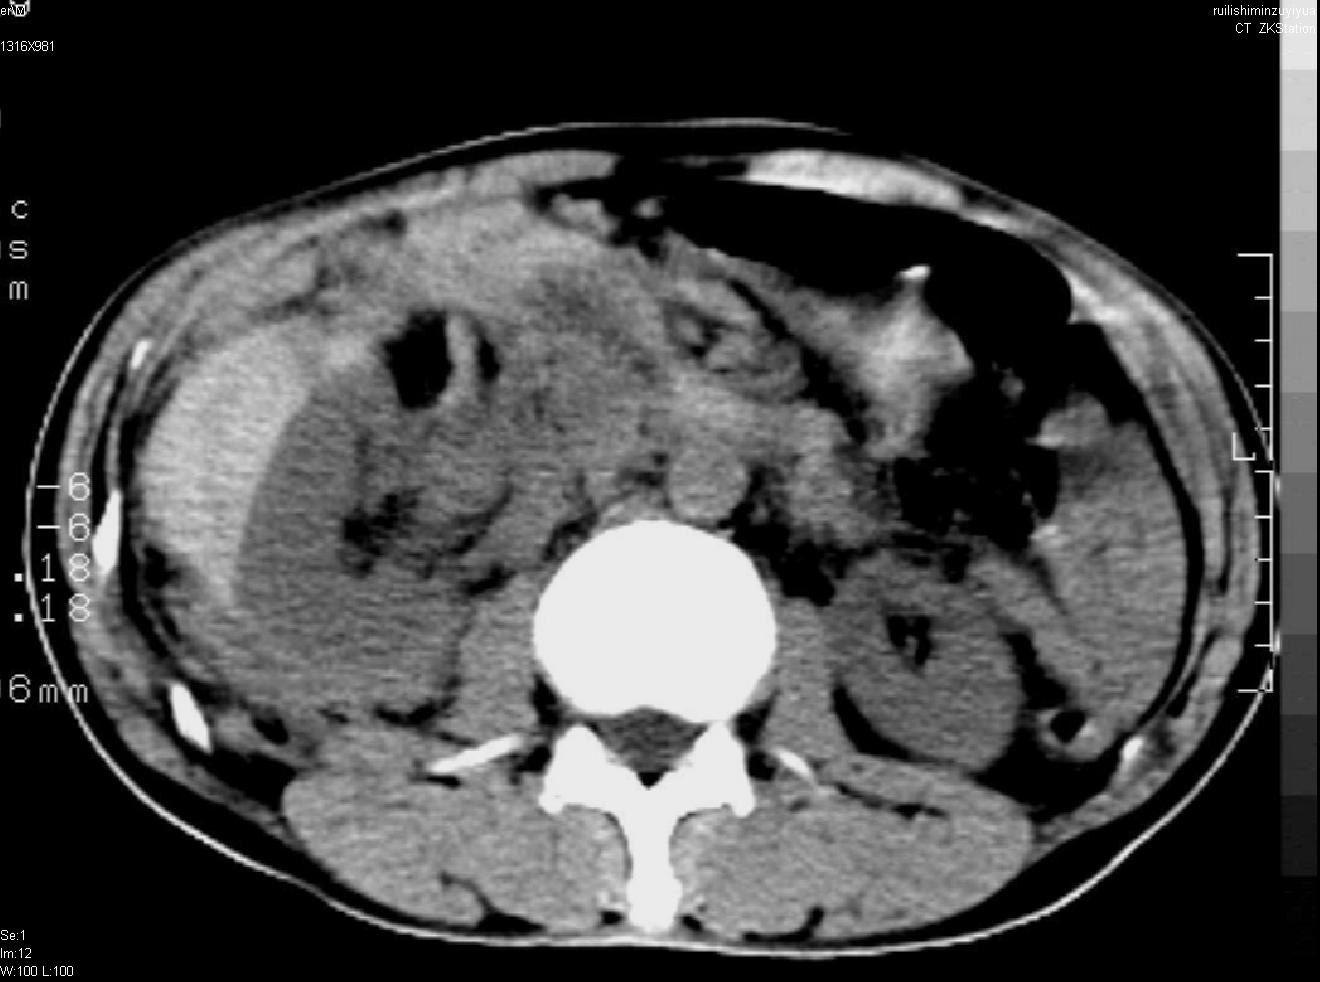

以下是引用liuyue在2007-12-3 6:27:00的发言:[br]右肾区可见密度不均匀、边缘欠清之肿块影,肾脏筋膜增厚,周围脂肪密度增高。右侧胸膜腔内可见少量液体密度影。考虑:1.右肾错构瘤(肾血管平滑肌脂肪瘤)可能性大。2.右侧少量胸腔积液。[br] 鉴别:1.肾脂肪肉瘤。2.肾平滑肌肉瘤。3.肾错构瘤恶变。

以下是引用dyqct在2007-12-3 7:38:00的发言:[br][quote]以下是引用liuyue在2007-12-3 6:27:00的发言:[br]右肾区可见密度不均匀、边缘欠清之肿块影,肾脏筋膜增厚,周围脂肪密度增高。右侧胸膜腔内可见少量液体密度影。考虑:1.右肾错构瘤(肾血管平滑肌脂肪瘤)可能性大。2.右侧少量胸腔积液。[br] 鉴别:1.肾脂肪肉瘤。2.肾平滑肌肉瘤。3.肾错构瘤恶变。